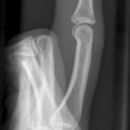

Bennett Fraktur